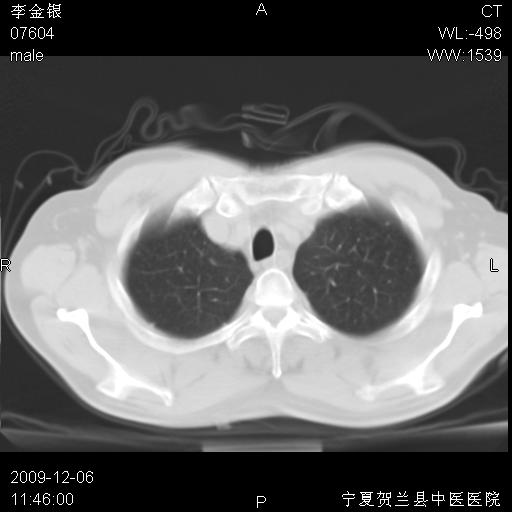

该病人 ,男,62岁,主因咳痰带血两天

考虑右肺中央型占位性病变并阻塞性肺炎.(右肺上叶支气管变窄),建议支纤镜检查.

考虑右肺中心型肺癌伴阻塞性肺炎及右肺门淋巴结转移,建议纤维支气管镜进一步检查。

支气管壁明显增厚 管腔狭窄,腔静脉后多个淋巴肿大,结合年龄病史考虑右肺上叶中央型肺癌并阻塞性肺炎

右肺上叶后段支气管阻塞,右上肺门占位,相应肺段阻塞性肺炎,右肺门有淋巴结肿大。诊断右肺上叶中心型肺癌,阻塞性肺肺炎、右肺门淋巴结转移。

右上叶支气管狭窄,管壁增厚,远端斑片状软组织影,病灶邻近叶间裂,叶间裂无移位。

诊断右肺中央型肺癌。

那个片影应该大部分都是病灶,病灶沿肺段支气管分支生长,后段完全显示不清、闭塞。若为不张应该伴有叶裂的移位,若为炎症应有空气支气管征。

右肺中心型肺癌伴阻塞性肺炎及右肺门与纵膈淋巴结转移很典型,可纤维支气管镜进一步检查

考虑右侧中央型肺癌伴右肺上叶后段阻塞性炎症、肺不张、右肺门和纵隔淋巴结肿大。

右肺上叶中心型肺癌,阻塞性肺炎、右肺门和纵隔淋巴结转移。